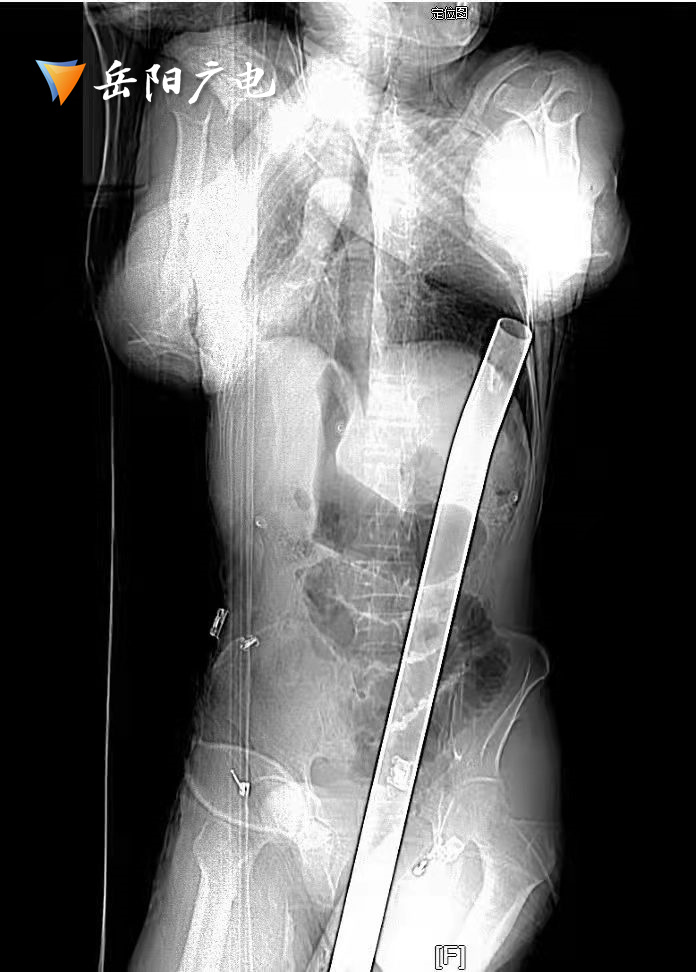

几天前,岳阳县村民刘师傅整理屋顶时,不慎从高空坠落,被1米多长的钢筋贯穿胸腹部。

(影像学照片)